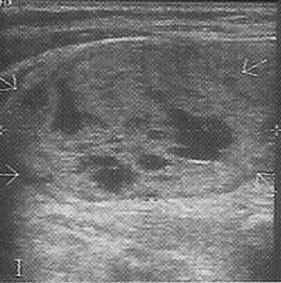

Ultrasonda nodülün içi tamamen sıvı ile dolu ise kistik nodül (şekil 1), tiroit kaynaklı doku ile dolu ise katı nodül (solit nodül) (şekil 2), hem doku hemde sıvı içeriyorsa karışık nodül (mikst nodül) (şekil 3) adını alır.

Şekil 1: Kistik nodül ![]() | Şekil 2: Katı nodül ![]() | Şekil 3: Karışık nodül ![]() |

Ultrasonda tiroit kanser riski bulguları: Çapı 2.5-3cm'den büyük olan katı (Şekil 4) ya da karışık nodüller, çapı 4cm'den büyük kistik nodüller, kenarları düzensiz (Şekil 5) ve/veya içinde küçük kireçlenme odakları bulunan nodüller (Şekil 6), içinde ve etrafında kan akımı artmış olan nodüller ve izlemler sırasında büyüyen nodüller riskli nodüllerdir. Bunlardan bir kaçının beraber bulunması riski arttırır.